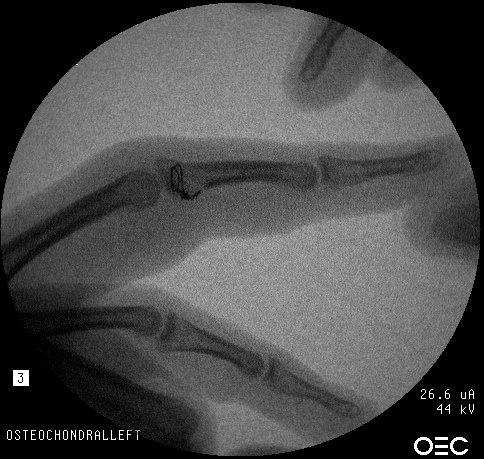

Intraoperative fixation and motion: Initial attempts of micro screw fixation were not successful, and wire cerclage was used:

This is a technically demanding procedure. Although the apparent bone defect seems triangular, it is better to start with a rectangular graft as in

this case

to avoid problems illustrated below:

Because of questionable stability of the fixation, a Dynamic Traction Splint for Proximal Interphalangeal Joint Fracture Dislocations was used: